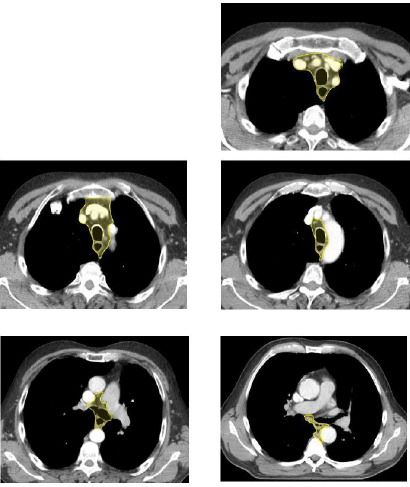

Contouring atlas: the elective lymph nodes

(Illustrated without margins for motion management)

Para-esophageal, paratracheal, pretracheal and mediastinal (anterior, retrotracheal, posterior mediastinal and trachea-bronchial) lymph nodes.

Above the carina, the CTV will encompass the entire trachea and extend radially to encompass the lower and upper paratracheal nodal stations which correspond to levels 2 and 4 in the IASLC staging atlas3). Above the aortic arch the anterior border of the CTV is defined by the sternum and clavicular heads to encompass pre-vascular nodes (IASLC level 3). Above the level of the thoracic inlet, the trachea should be excluded from the CTV (unless the 1 cm radial margin to the esophagus requires it).

For distal tumors in which the CTV extends superiorly to the mediastinum only to respect the cranial margin to the primary tumor or to para-esophageal lymph node metastases, the superior nodal stations except for the para-esophageal lymph nodes need not to be included.